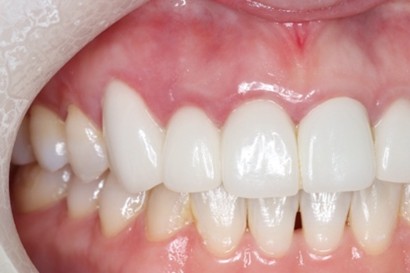

Before

抜歯およびRidge Preservation時の口腔内写真

抜歯時に頬側の骨の大きな欠損を認めた。サイトランス®を使用したRidge Preservation、Cytoplast®※を使用し抜歯窩を被覆

骨の再生が起きており十分な骨幅を認める

補綴後の口腔内写真

マイクロスコープにて歯の破折を確認し、患者さんとも相談の上、抜歯しインプラント埋入となった

破折歯を抜歯した場合、今回のケースのように骨の吸収が著しく生じていることが多く、このままではインプラント周囲に十分な骨幅(理想的にはプラットフォームから2mmの骨幅)を維持することができないためRidge Preservationは非常に有効な手法であると考える。